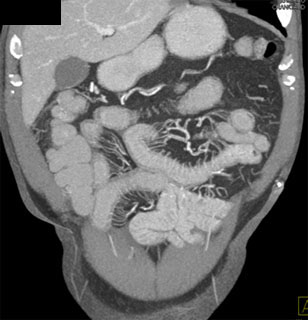

The most likely dx in this patient with right lower quadrant pain is?

small bowel lymphoma

metastatic melanoma

crohn's disease

radiation enteritis